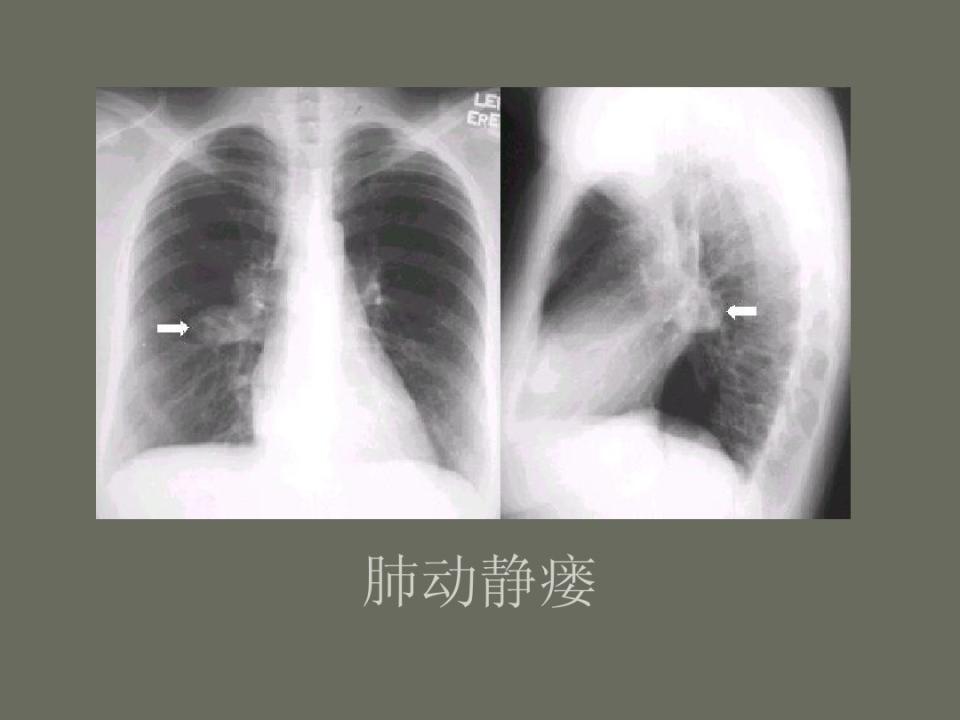

肺部先天性疾病的影像诊断